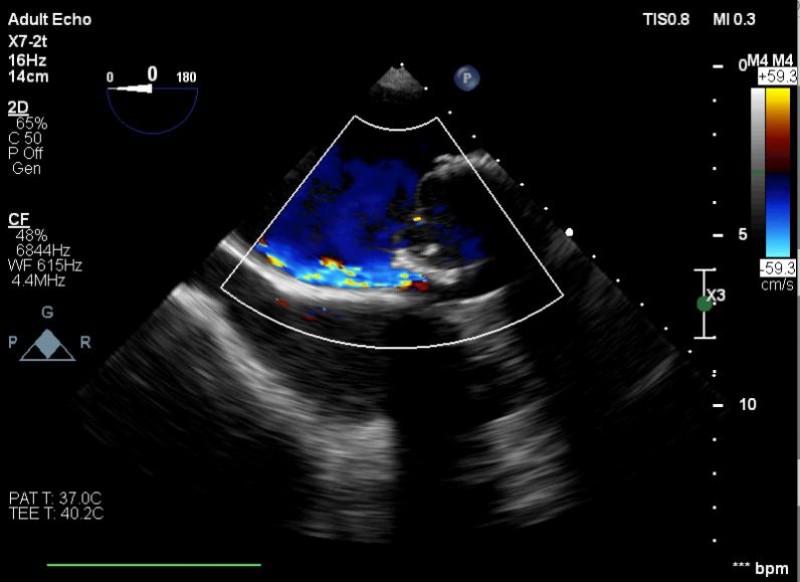

Yapılan işlemi gerçekleştiren ekipte yer alan Prof. Dr. Halil Kısacık, Doç. Dr. Eyüp Avcı, Doç. Dr. Tarık Yıldırım ve Doç. Dr. Özgen Şafak konu hakkında açıklamalarda bulundu. Daha önce kalp kapakçığı değişim ameliyatı olan hastada takılan kapağın kenarından ayrılmasıyla kan kaçağı (paravalvuler leak) meydana geldiğini belirten öğretim üyeleri, Kardiyoloji Anabilim Dalına başvuran hastaya, Türkiye’de sayılı kalp merkezinde yapılan ve önemli düzeyde cerrahi deneyim gerektiren paravalvüler kaçak kapatılması işlemi uygulandığını dile getirdi. İşlemin sadece girişimsel kardiyologlar tarafından yapıldığının altını çizen öğretim üyeleri, işlem sırasında hastanın kalbi durdurulmadan ve göğüs kafesi kesilmeden, kasığından girilerek yapay kalp kapağındaki kaçağın ameliyatsız kapatıldığını söyledi.